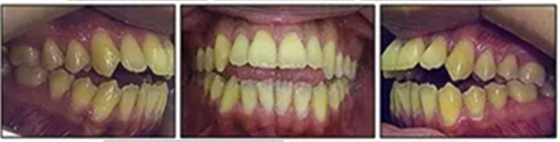

面相示:右側面部不對稱,閉唇不全,下頜骨順時針旋轉,凸面型;張閉口時無下頜骨偏斜;雙側關節(jié)檢及骨擦音。

口內(nèi)相示:口腔衛(wèi)生可,下頜前牙區(qū)輕度擁擠伴齦上牙石,無齲齒、牙齦炎;開合,覆蓋5mm,休息時舌后退位,吞咽時舌前伸。

口外相:正畸治療取得了良好的唇功能,前牙開合得到關閉,面部輪廓改善;側貌的凸度是由于患者頦部過小且后縮所致。

口內(nèi)相及模型:雙側磨牙、尖牙I類關系,良好的牙尖交錯關系,覆合、覆蓋正常。